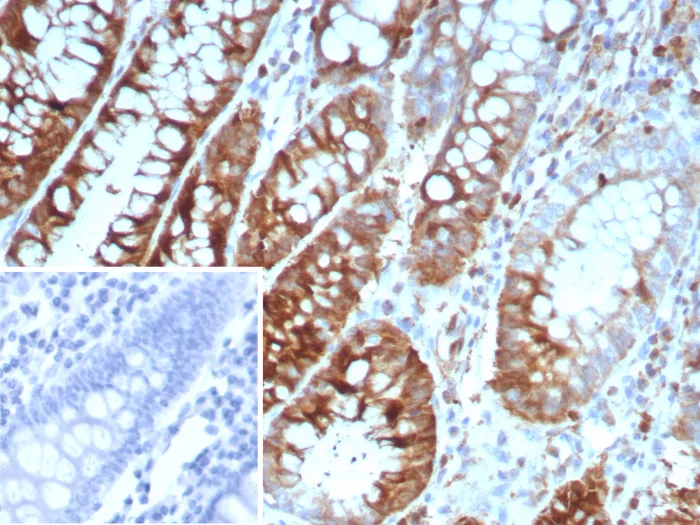

Formalin-fixed, paraffin-embedded human colon carcinoma stained with Stathmin 1 Mouse Monoclonal Antibody (STMN1/8439). Inset: PBS instead of primary antibody; secondary only negative control.

Op18 (for oncoprotein 18, also designated stathmin, prosolin or metablastin) is a conserved, Tubulin-associated, intracellular phosphoprotein. Many different phosphorylated forms of Op18 are observed, and it is expressed as two different isoforms. Op18 is considered a critical regulator of microtubulin dynamics and is downregulated by p53. It serves as a transducing protein, via phophorylation, for a variety of cell signaling pathways and is involved in both mitosis and differentiation.Op18 is present in many cancers, including breast carcinomas, and is highly expressed in acute leukemias of different subtypes.